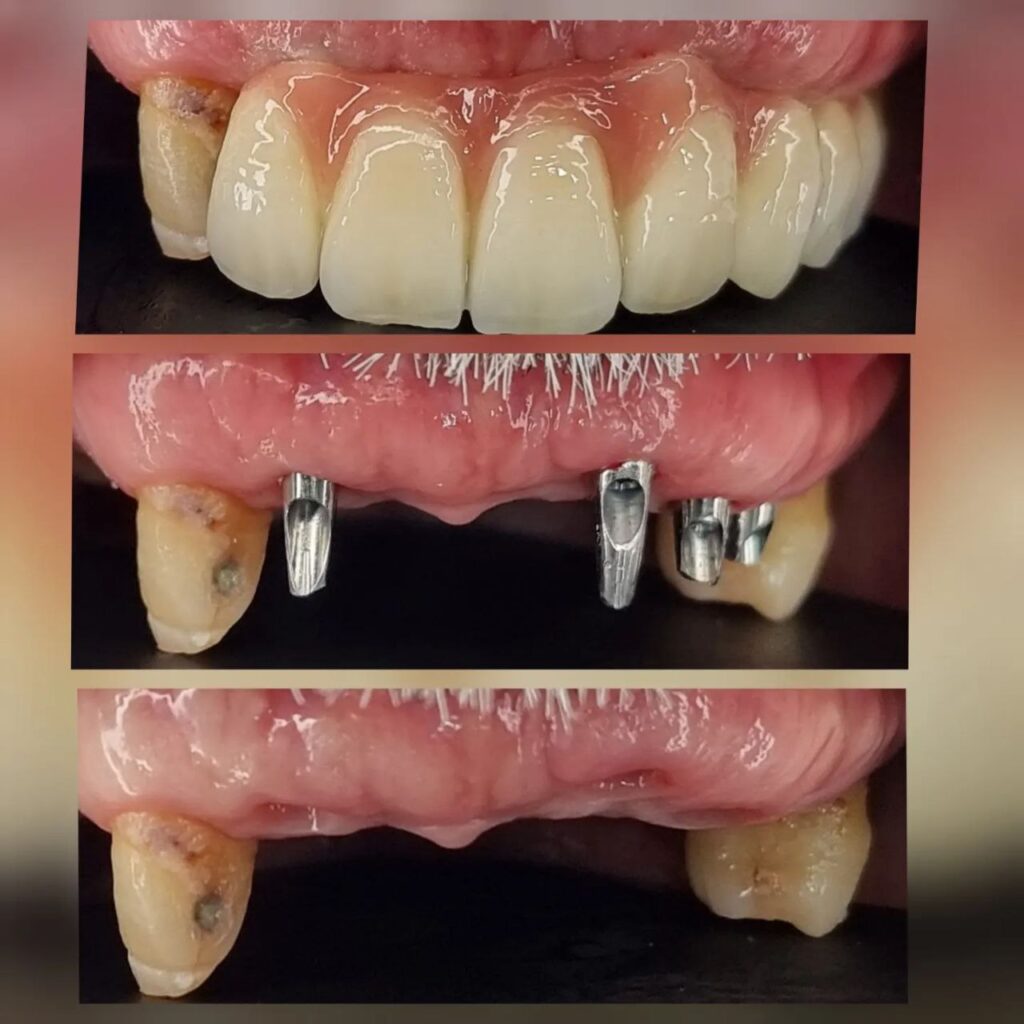

کاشت ایمپلنت دندان

اطمینان حاصل کردن از اینکه دندانهایتان به نحوی زیبا و طبیعی جایگزین شدهاند، از اهمیت بسیاری برخوردار است. ایمپلنت دندان به عنوان یک روش درمانی دائمی در دندانپزشکی شناخته میشود که حاصل آن، یک دندان زیبا و طبیعی در دهان شما خواهد بود.

هرچند که این روش درمانی هزینهی بیشتری نسبت به روشهای دیگر دارد، اما ارزش زیبایی که ایجاد میکند، قابل انکار نیست. ایمپلنتها به قدری شبیه به دندانهای طبیعی هستند که به سختی میتوان آنها را از دیگر دندانها تشخیص داد.